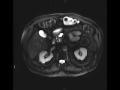

Side-branch Intraductal Papillary Mucinous Neoplasm (IPMN)

Multiple MR images demonstrate a cystic lesion arising from the pancreatic neck, apparently communicating with the adjacent pancreatic duct, representing a sidebranch IPMN